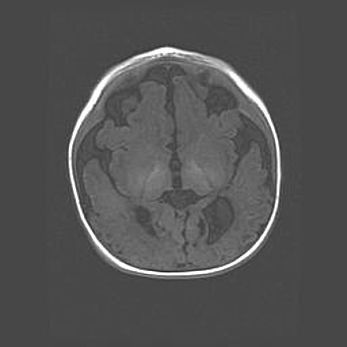

Открытая гидроцефалия.

Возраст: 6 месяцев 15 дней

Вес: 6200 г

Пол: женский

Окружность головы: 41 см

Срок гестации: 38 недель

Гидроцефалия головного мозга у новорожденных – это скопление избыточного количества цереброспинальной жидкости в головном мозге. Ее избыточное скопление в мозге приводит к патологическому расширению желудочков мозга (четырех полостей, расположенных в глубине белого вещества мозга, заполненных цереброспинальной жидкостью и связанных узкими проходами).

Открытый тип гидроцефалии (сообщающаяся) наблюдается тогда, когда нарушен механизм всасывания ликвора в системный кровоток. При этом типе причиной заболевания чаще всего является перенесенные ранее инфекции (например: менингит),  либо же наличие крови в субарахноидальном пространстве.